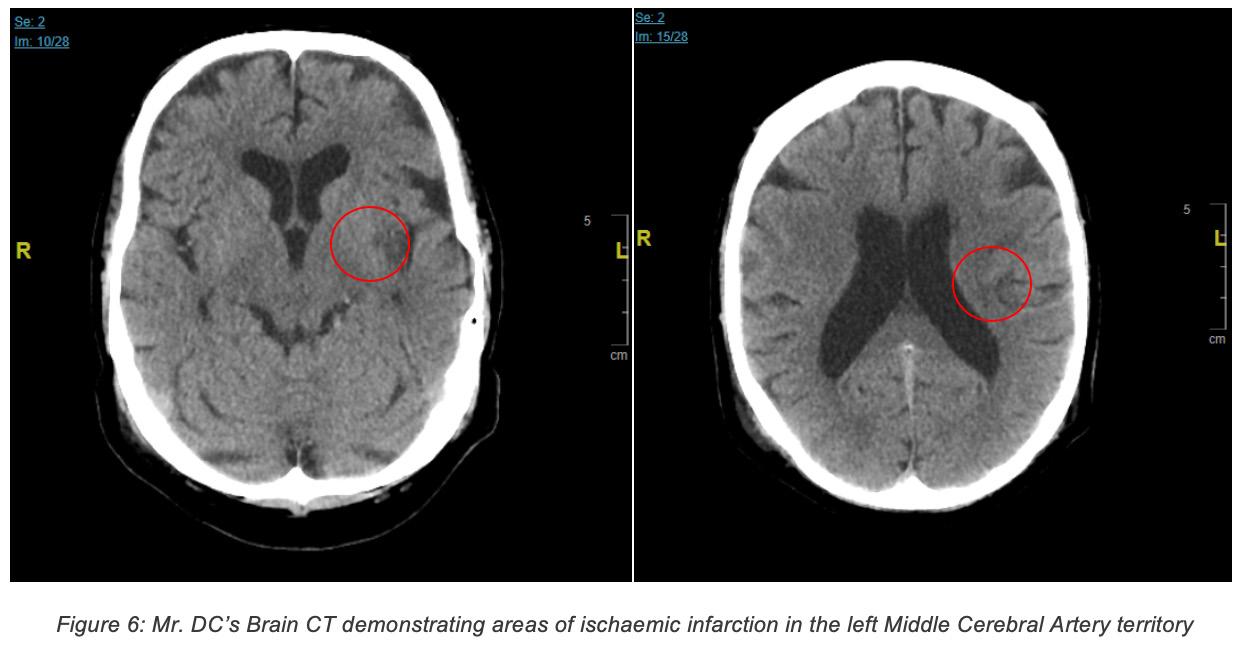

Findings: • The CT brain revealed an ischaemic stroke of the middle cerebral artery territory. CT brain results are shown below: